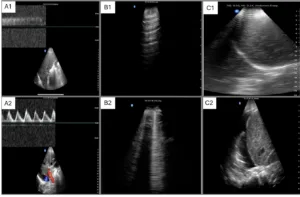

Interestingly, the patient lacked pedal edema or shortness of breath. A formal echocardiogram demonstrated reduction of left ventricular ejection fraction from a baseline of 37% to ~30%, new right ventricular enlargement with interventricular septal flattening (D-sign), and severe functional tricuspid regurgitation, suggestive of fluid overload (Figure 3). The patient history was not suggestive of pulmonary embolism. A nuclear medicine stress test was negative for ischemic changes. Over the subsequent three days, the nephrology team performed daily ultrafiltration, resulting in removal of 8 liters of fluid (net negative 4.5 liters on day 3). At the end of the second session, the nephrology team performed a follow up VExUS scan that showed significant improvement in the congestion. The portal vein was completely normalized, whereas the hepatic vein showed mild congestion with S-wave less than D-wave. A simultaneous ECG tracing was used to avoid errors in misidentification of the waves (Figure 4).

Figure 3. Formal echocardiogram images demonstrating (A) interventricular septal flattening on parasternal short axis view and (B) qualitatively severe tricuspid regurgitation.

Additionally, cardiac POCUS revealed a rounded left ventricle in the parasternal short-axis view. This indicated resolution of the D-sign along with significant improvement in tricuspid regurgitation (Video S1 and S2). Although serum transaminases showed improvement during this time (ALT and AST decreased from 184 to 98 U/L and 156 to 59 U/L, respectively), it cannot be solely attributed to reduction in congestion, as the patient was concurrently diagnosed with a hepatitis C infection (Hep C RNA 141,000 IU/mL). The patient’s weight after the third dialysis session was conveyed to his outpatient nephrologist to assist in adjusting dry weight.